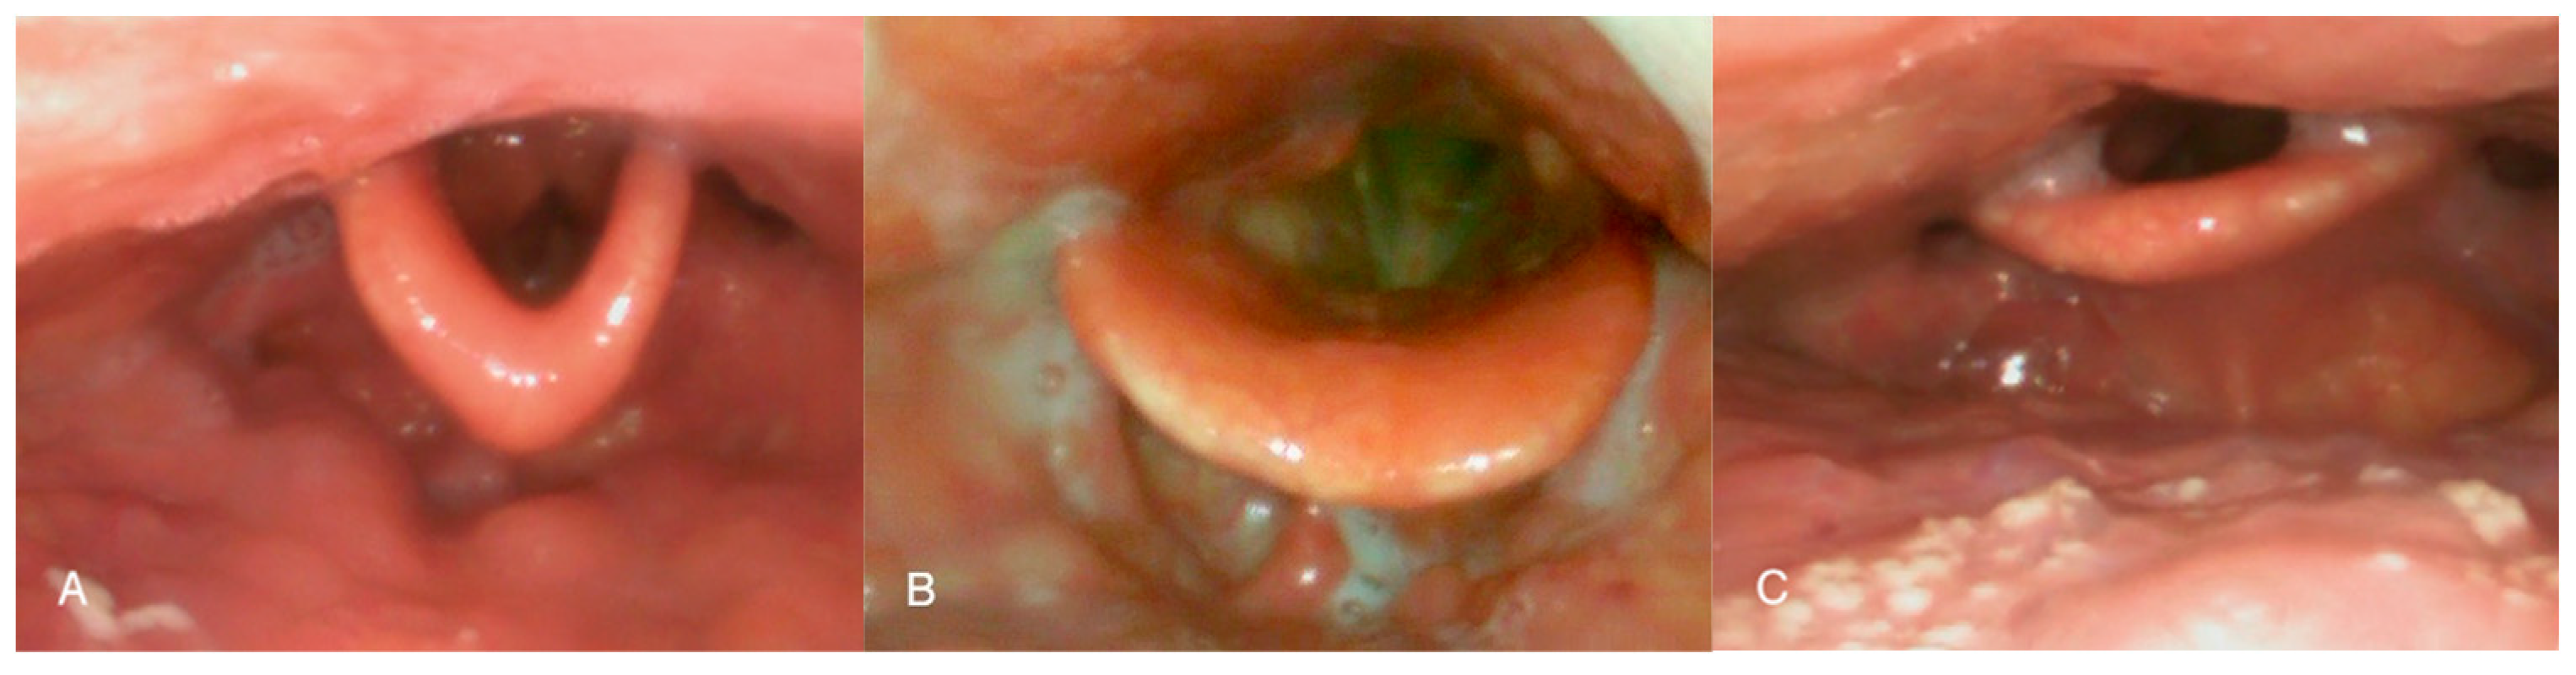

The epiglottis is an important anatomical structure that was largely overlooked in early research on obstructive breathing disorders. However, more recent studies have demonstrated that it plays a significant role—either independently or in combination with other pharyngeal structures [7]. This has been further supported by the introduction of routine pre-operative assessments, particularly drug-induced sleep endoscopy (DISE), which has revealed that partial or complete obstruction at the level of the epiglottis occurs in approximately 20% to 40% of OSA patients [8,9]. Although it was long believed that such obstructions could not be suspected based solely on awake examination, careful observation may provide clues regarding epiglottic collapse. In a previous study, obstructions at this level were shown to occur more frequently in patients with a flat-shaped epiglottis—Figure 1C [10].

Figure 1. Different epiglottis shapes. Type 1—omega-shaped epiglottis (A); Type 2—normal concave epiglottis (B); and Type 3—flat epiglottis (C). Adapted from ref. [10].